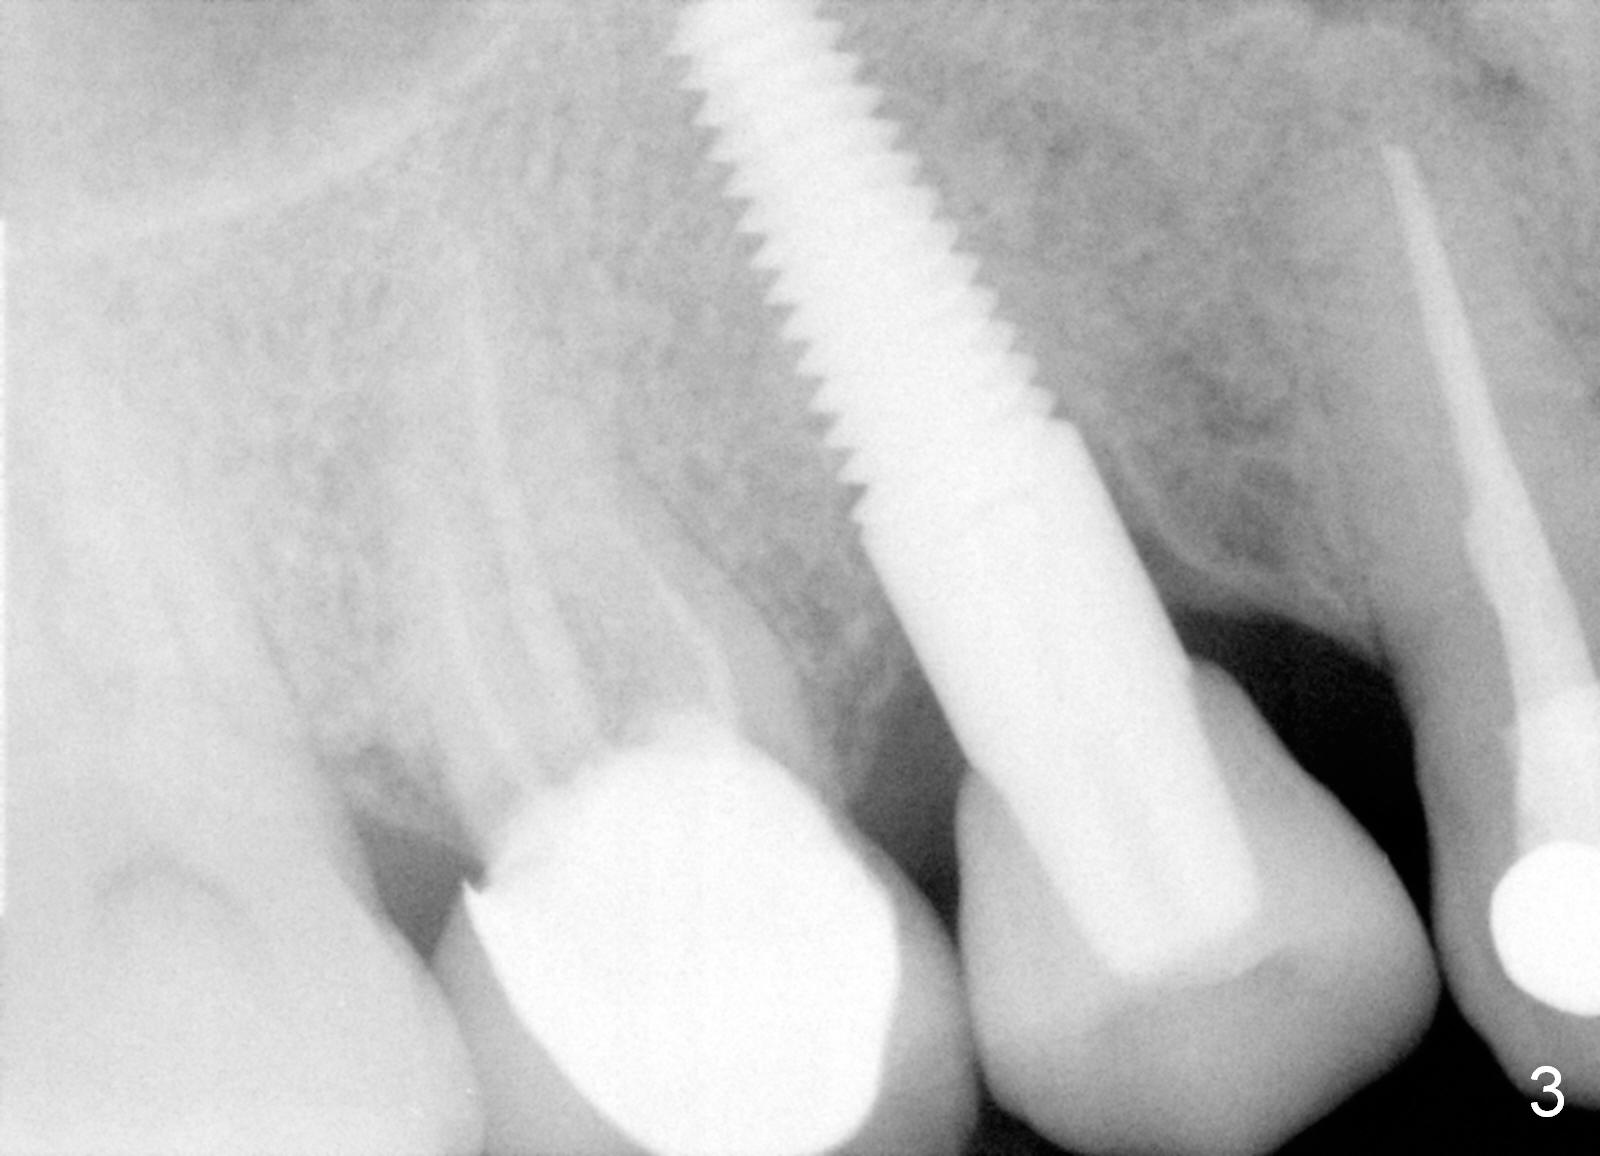

A 47-year-old man has multiple restoration. The crown of the tooth #3 has been recemented several times in the last 3 years (Fig.1). Before placement of an immediate implant at #3 (Fig.2), the root of the adjacent tooth is diagnosed to have crack and replaced by an immediate implant (Fig.3).